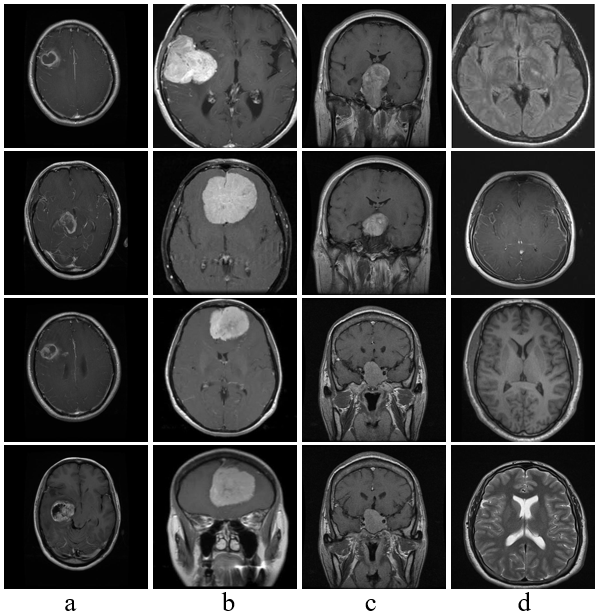

本研究收集了两个包含正常和肿瘤脑部影像的数据集,均来自开源平台Kaggle,分别命名为Dataset-1和Dataset-2.其中,Dataset-1数据集包含3 762张MRI影像(有肿瘤1 683张,无肿瘤2 079张),该数据集用于实验中二分类任务.Dataset-2数据集包含7 023张MRI影像(脑膜瘤1 621张,胶质瘤1 645张,垂体瘤1 757张,无肿瘤2 000张),该数据集的图像数量较为均衡,用于实验中三分类任务的训练和评估.图6展示了从Dataset-1和Dataset-2数据集中抽取的正常与肿瘤脑部影像的样本,直观地展示了本研究使用的影像类型和质量.通过这种系统的实验流程和深入的数据分析,旨在提高颅内肿瘤分类的准确性,为临床诊断提供有效的辅助工具.

图6

从Dataset-1和Dataset-2数据集中抽取的正常与肿瘤脑部影像的样本. a: 胶质瘤; b: 脑膜瘤; c: 垂体瘤; d: 无肿瘤

Fig. 6

Samples of normal and tumor brain images extracted from Dataset-1 and Dataset-2. a: Glioma, b: Meningioma, c: Pituitary, d: No tumor